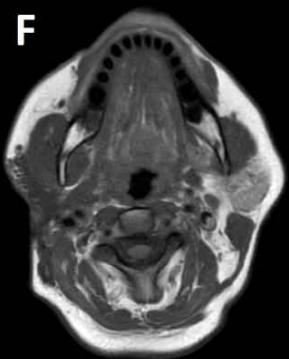

Figure/Patient 3

An 8 year-old girl with prior surgical excision of a right latero-cervical lymphangioma presenting with a new-onset tumefaction within the same region. MRI scans show a 9-10 cm subcutaneous multilocular lesion, extending between two virtual planes crossing the retro-molar trigone and the thyroid respectively, with deep invasion of parapharyngeal spaces cranially and the space between the submandibular gland and the vascular peduncle of the neck caudally. The lesion appears hyper-intense on T2 weighted scans with (A-B) and without (C-D) fat suppression, hypo-intense on T1 weighted scans with (E) and without (F) fat suppression and hyper-intense on DWI scans with high B values (G). Diagnosis of loco-regional recurrence of cystic lymphangioma is done.